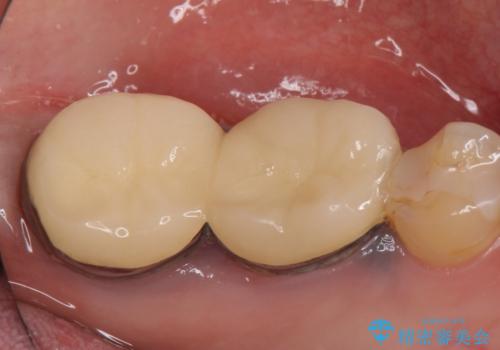

- 右下奥歯の歯茎がよく腫れるので診て欲しいといらっしゃった方の症例です。

診査の結果、右下6番目の根尖病変を認めたため再根管治療を行いました。

また右下7も根管充填が不十分なため再根管治療を行いました。

症状の消失を確認後、オールセラミッククラウンによる補綴を行いました。